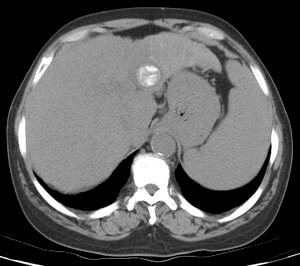

68 year old male with a solitary HCC in the left hepatic lobe who underwent staged procedures for treatment.

Comment: The early enhancing lesion in the left hepatic lobe was difficult to see with ultrasound and similarly difficult to see on a non-contrast CT scan. As a result, image-guided RF ablation would be difficult. Therefore, we first performed classic-TACE with ethiodol and then used the persistent opacification of the tumor after TACE to guide the ablation procedure.